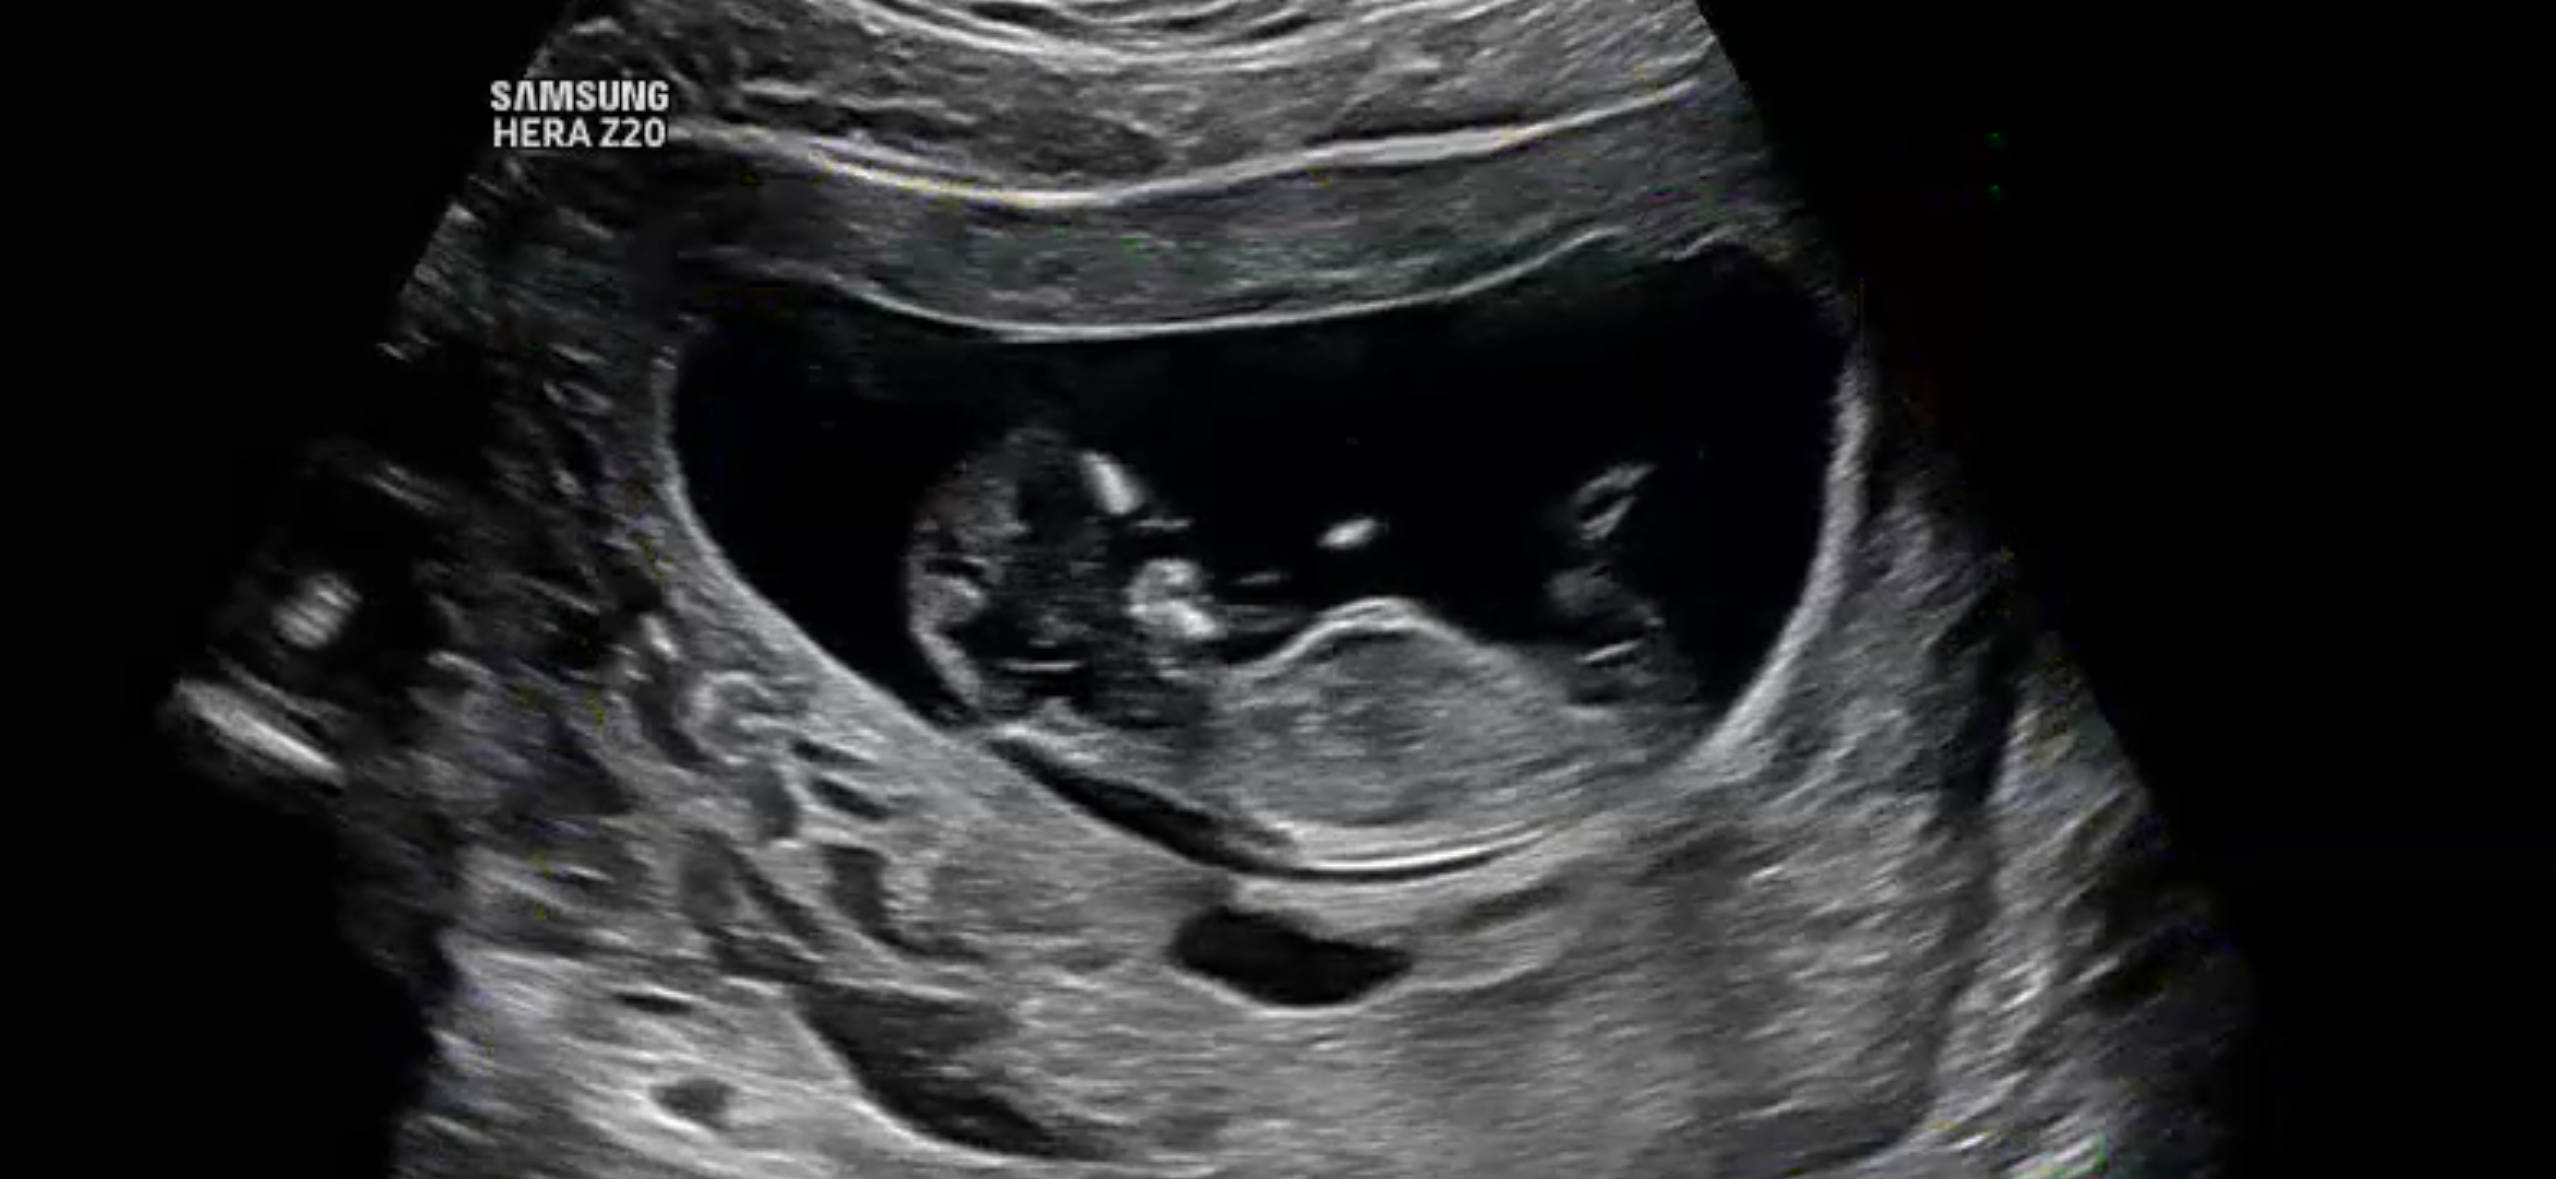

저도 드디어 12주차 아들일까요 딸일까요?

초음파 사진을 올리면 AI가 무료로 예측해줘요